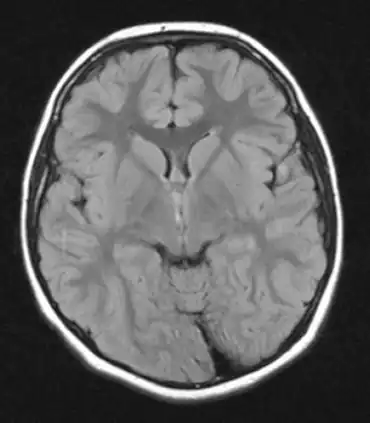

| MRI of individual with Sydenham chorea. | |

- Magnetic resonance imaging or computed tomography scan of the brain (alterations in caudate nucleus and putaminal enlargement have been described in some patients)[11][12]